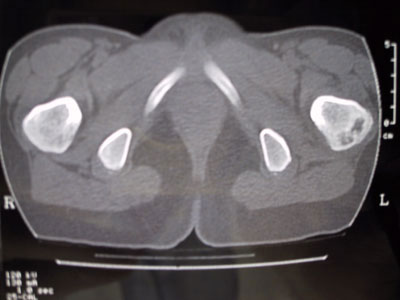

Alla TAC viene evidenziata una zona di lisi a livello del collo femorale in corrispondenza del gran trocantere.

Si segnala persistenza di ipotrofia muscolare alla coscia di sinistra. Si consiglia di eseguire scintigrafia ossea e di programmare biopsia. L'esame scintigrafico dello scheletro, eseguito dato il quesito clinico anche con tecnica trifasica e tomografica al bacino, evidenzia in fase osteotropa iperaccumulo del tracciante a gradiente piuttosto intenso in corrispondenza del gran trocantere del femore di sinistra, reperto che appare riconoscibile già nelle immagini precoci della fase dinamica e di pool ematico e che nelle immagini tomografiche interessa tutta la regione supero-laterale della porzione trocanterica del femore ed in parte il collo femorale, arrivando infero-lateralmente fin quasi al piccolo trocantere.